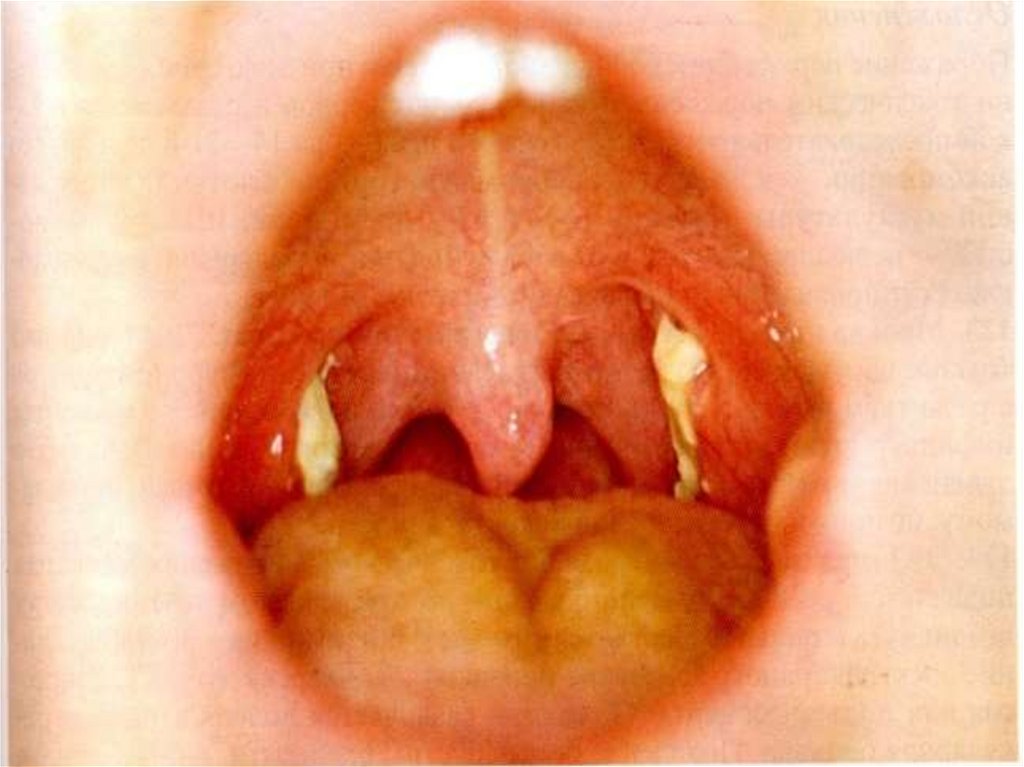

ДИФТЕРИЯ МИНДАЛИН И ГЛОТКИ

Легкая форма:

субфебрильная температура тела;

умеренная слабость при нормальной гемодинамике;

незначительная боль в горле, нормальная или гиперемия и

отек миндалин и слизистой глотки;

наличие на миндалинах мелких пленок или небольшой

сплошной пленки;

увеличение и умеренная болезненность при пальпации

подчелюстных лимфоузлов;

по клиническим признакам врачами общей практики

диагносцируется как тонзиллит, фарингит, ОРВЗ !!!

Средне-тяжелая форма дифтерии ротоглотки:

острое начало, лихорадка до 38 – 38,5 гр.С, слабость, жажда.

боль в мышцах и суставах, головная боль, снижение аппетита.

умеренная боль в горле при глотании.

бледные кожные покровы, иногда акроцианоз

отек миндалин и слизистой ротоглотки, обнаружение

фибринозной пленки со склонностью к распространению;

увеличение и болезненность подчелюстных лимфоузлов;

отек подкожной клетчатки шеи (до ключицы)

относительная тахикардия, склонность к гипотонии,

систолический шум на верхушке;

миокардит, мононеврит (чаще парез мягкого неба).

Тяжелая форма дифтерии ротоглотки:

фибринозная пленка на миндалинах с выходом за их пределы

(распространенная или комбинированная форма дифтерии);